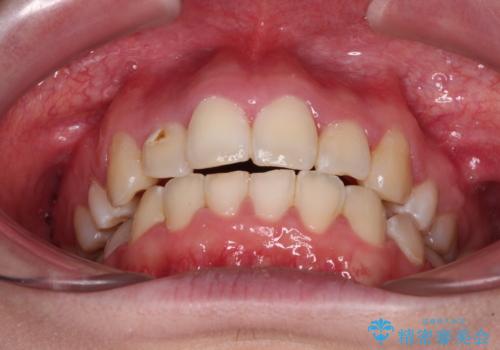

- 骨格的な咬み合わせのズレ、前歯のデコボコとクロスバイトを気にして来院された患者様です。

口元の突出感が若干あり口が閉じにくく、デコボコが強いため、上下左右の小臼歯計4歯を抜歯し、ワイヤー装置による矯正治療を行うこととしました。

治療中に舌の突出癖が改善されず、下顎前歯が著しく前方に突出して反対咬合となってしまう局面がありました。

アンカースクリューを使用しながら舌癖の改善を図り、何とか咬み合わせを改善することができました。